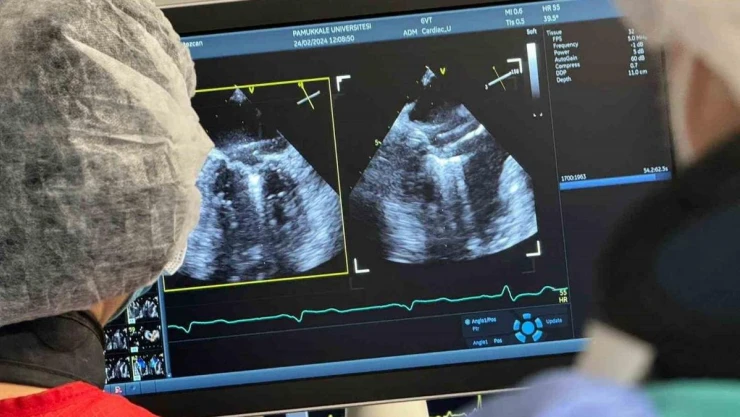

DENİZLİ (İHA) – Pamukkale Üniversitesi (PAÜ) Hastanesi Kardiyoloji Anabilim Dalı, Denizli'de ilk defa yapılan mitraklip işlemini başarıyla gerçekleştirdi.

Ameliyatsız mitral kapak yetmezliği tamiri (Mitraklip) işlemi, Denizli’de ilk defa Pamukkale Üniversitesi Hastanesinde Kardiyoloji Ana Bilim Dalı Öğretim Üyeleri Prof. Dr. Doğu Kılıç, Doç. Dr. İpek Büber ve Dr. Öğretim Üyesi Işık Tekin tarafından yapıldı.